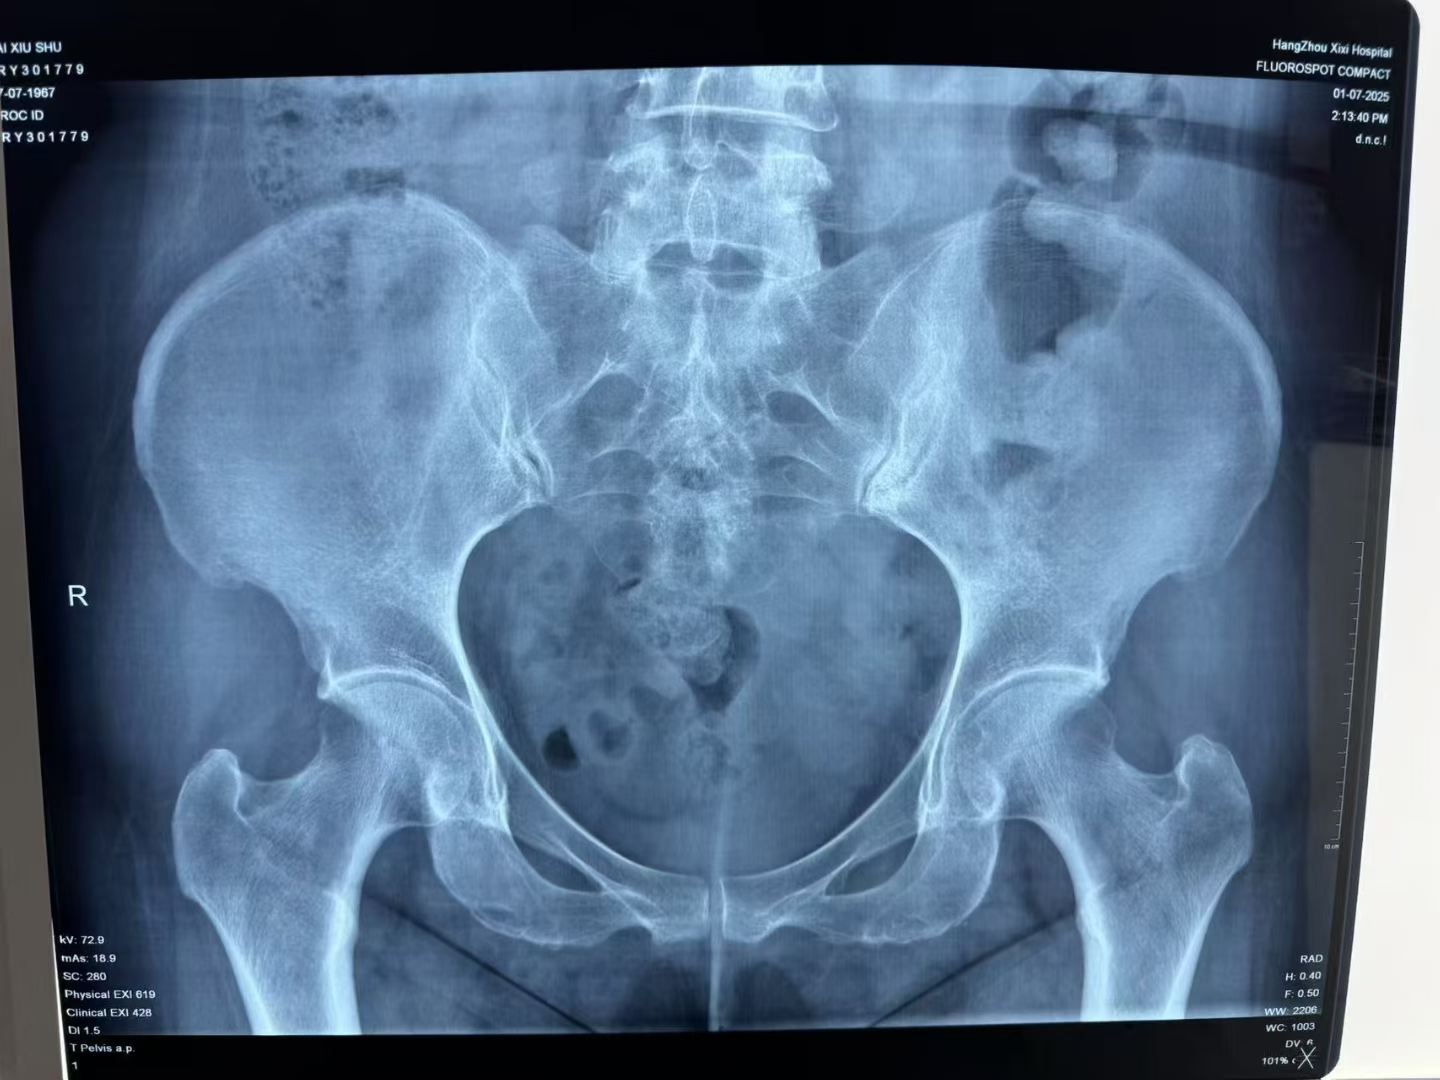

骶髂关节炎